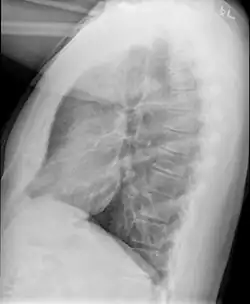

Causes include breathing in toxic fumes, respiratory infections, connective tissue disorder or complications following a bone marrow or heart-lung transplant.[1] Symptoms may not occur until two to eight weeks following toxic exposure or infection.[1] The underlying mechanism involves inflammation that results in scar tissue formation.[1] Diagnosis is by CT scan, pulmonary function tests or lung biopsy.[1] A chest X-ray is often normal.[4]

Bronchiolitis obliterans is often diagnosed based on the symptoms of obstructive lung disease following lung injury. The definitive diagnosis is through biopsy, but due to the variable distribution of lesions, leading to falsely negative tests, and invasive nature of this procedure it is often not performed.[6][11] Several tests are often needed to diagnose bronchiolitis obliterans, including spirometry, diffusing capacity of the lung tests (DLCO), lung volume tests, chest X-rays, high-resolution CT (HRCT), and lung biopsy.[11][4]

Medical imaging

Early in the disease chest radiography is typically normal but may show hyperinflation.[6] As the disease progresses a reticular pattern with thickening of airway walls may be present.[4][6] HRCT can also show air trapping when the person being scanned breathes out completely; it can also show thickening in the airway and haziness in the lungs.[11] A common finding on HRCT is patchy areas of decreased lung density, signifying reduced vascular caliber and air trapping. This pattern is often described as a "mosaic pattern", and may indicate bronchiolitis obliterans.[6]